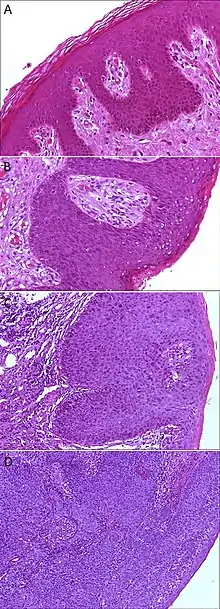

A. Normal histology, negative for anal intraepithelial neoplasia lesion (AIN)

B. Low-grade dysplasia, here called low-grade squamous intraepithelial lesion (LSIL)

C. High-grade dysplasia, here called high grade squamous intraepithelial lesion (HSIL)

D. Squamous cell carcinoma, infiltrating the stroma (middle and left in image), and HSIL (right in image)